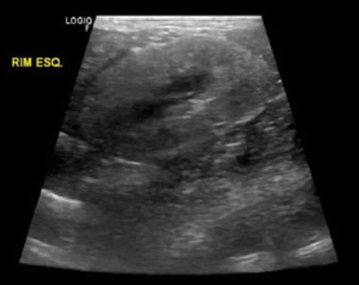

• 초음파 검사

피질, 수질 경계가 없음, hyperechoic